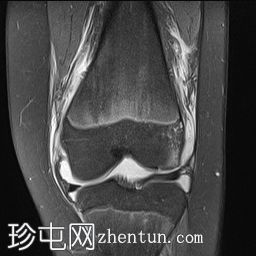

轴位PD序列

脂肪抑制序列

轴位

T1加权像

关节内大量积血,可见血细胞比容增高征。股骨外侧髁前部及髌骨内侧可见挫伤性微骨折。髌骨内侧支持带及髌股内侧韧带水肿增厚。髌骨内侧关节面下关节软骨浸润,提示I期骨软骨损伤。

髌骨外侧隐窝可见游离体,其信号强度与关节软骨一致,提示髌骨关节软骨外剥离损伤。股骨滑车和股骨关节软骨正常。

胫骨近端和腓骨骨骺以及股骨远端延伸至干骺端的骨骺周围可见局灶性骨髓水肿。这些提示存在局灶性骨骺周围水肿区。

十字韧带和侧副韧带正常。半月板正常。股四头肌腱和髌腱正常。

该病例具有短暂性髌骨外侧脱位复位损伤的特征性表现,包括预期的骨挫伤模式、内侧髌骨支持带/内侧髌股韧带损伤、髌骨骨软骨损伤以及髌骨软骨游离体。